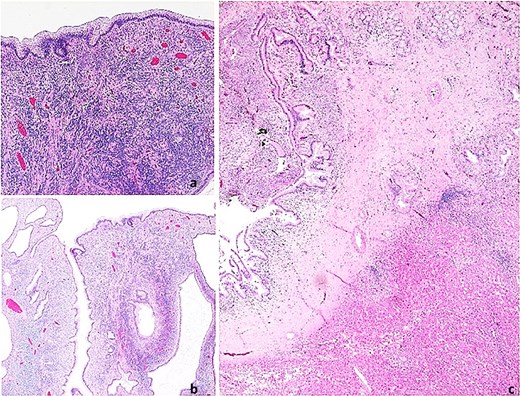

Pathological analysis confirmed MCN-L with biliary tract invasion. The tumor measured 1 centimeter with a pedicle extending over 5 centimeters into the bile duct. It was characterized by microcystic structures lined by mucin-producing columnar epithelium with basal nuclei, no atypia, and ovarian-like stroma under the epithelium (Fig. 4).

Histopathological images. Mucinous cystic neoplasm of the liver. (a) Neoplasm with a thick fibrous pedicle anchored in the hepatic parenchyma; (b) Multilocular neoplasm with compact cellular stroma; (c) Mucin-producing columnar epithelial lining and underlying ovarian-type hypercellular stroma.